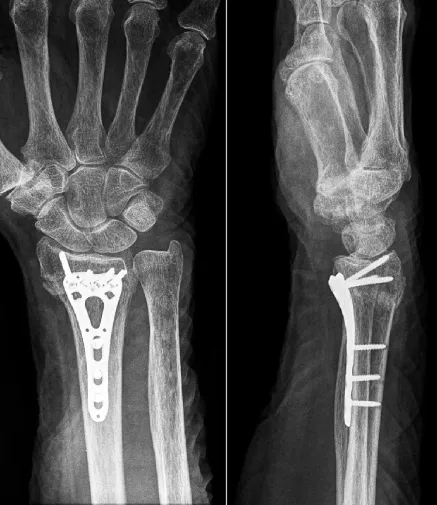

植入鋼板:將一塊金屬板固定在患者橈骨遠端的骨折處,然後使用螺釘將其固定。這個過程可以幫助保持骨折處的穩定性,使骨折得以癒合。

鋼釘內固定:使用一根鋼釘將骨折的兩個部分連接在一起,這個過程可以幫助保持骨折處的穩定性,使骨折得以癒合。